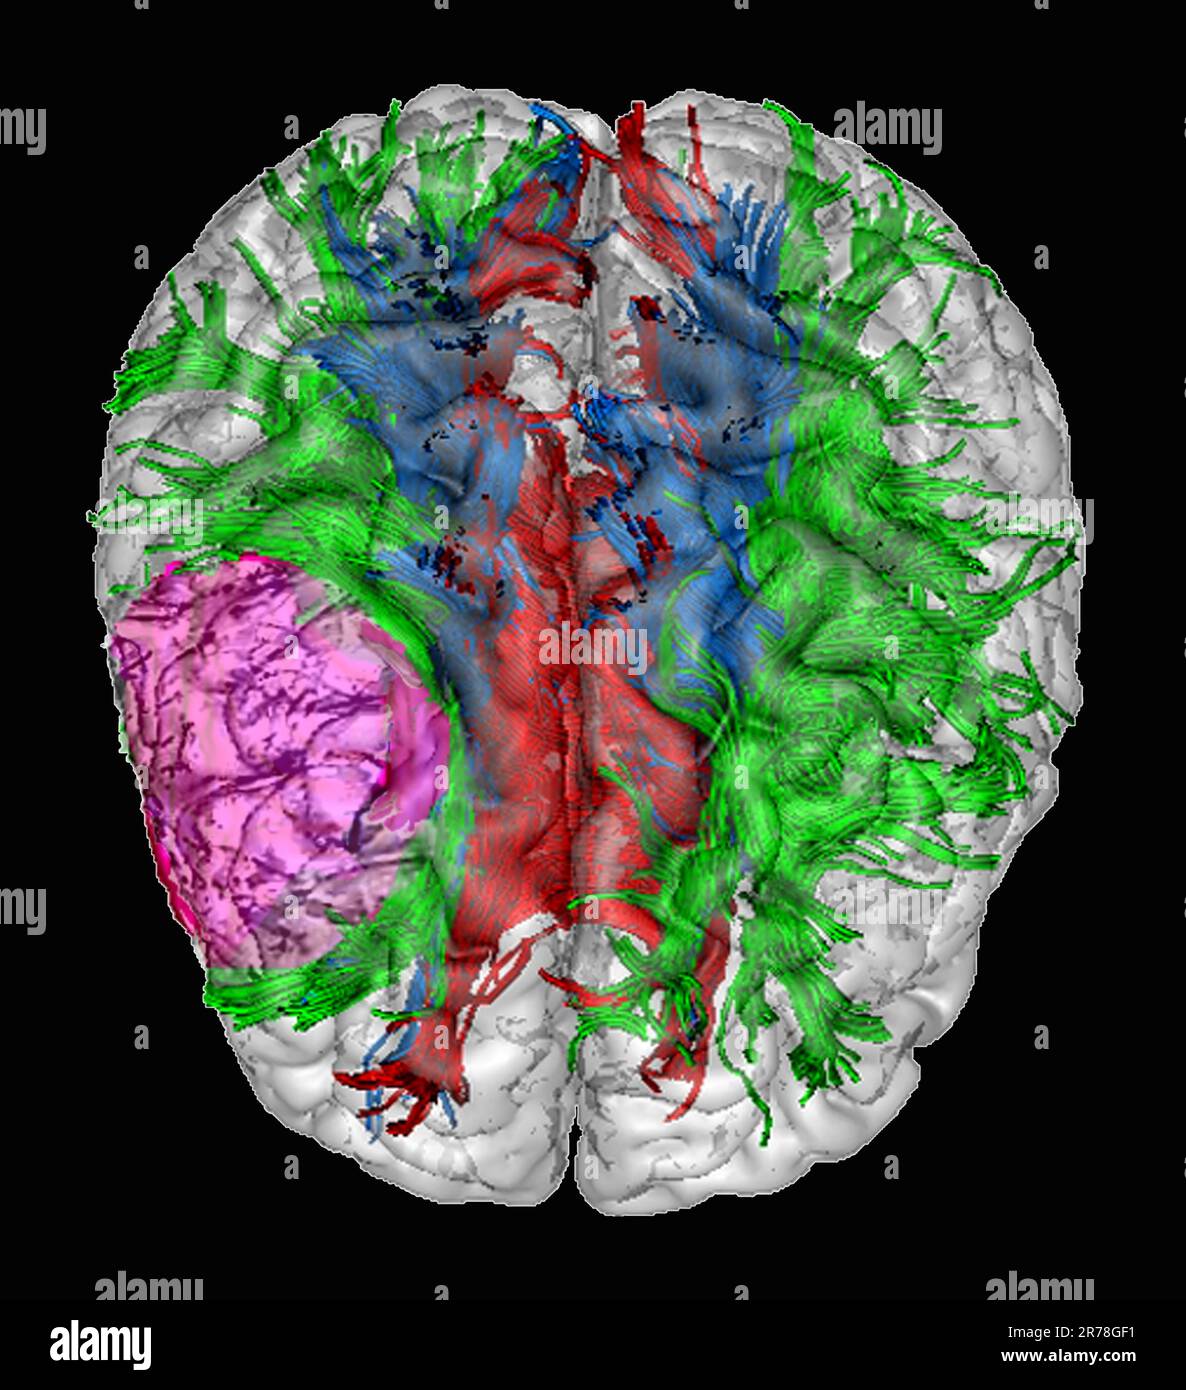

Wenn wir von einer Marklagerläsion sprechen bedeutet das, dass Ihr Hirn an genau dieser bestimmten Stelle stark, leicht oder mittelschwer beschädigt ist Eine Hirnläsion ist eine Art Anomalie im Gehirn , die normalerweise durch eine Krankheit oder Verletzung verursacht wird 1 Was ist eine Läsion? 2 Ursachen 3 Wann zum Arzt? 4 Symptome und Verlauf 5 Diagnose 6 Komplikationen 7 Behandlung und Therapie 8 Aussicht und Prognose 9 Quellen

Präfrontaler Cortex Anatomie und Klinik MediKarriere. Eine Hirnläsion ist eine Art von Anomalie im Gehirn, die normalerweise durch eine Krankheit oder Verletzung verursacht wird 1 Was ist eine Läsion? 2 Ursachen 3 Wann zum Arzt? 4 Symptome und Verlauf 5 Diagnose 6 Komplikationen 7 Behandlung und Therapie 8 Aussicht und Prognose 9 Quellen

SLAP Läsion Was ist das? Was kann man dagegen machen? Operation und Physio. Wie ernst sind Hirnläsionen und wie werden sie behandelt? Hier finden Sie Informationen über diese verwirrend und beunruhigend Gesundheit Die Symptome einer Hirnläsion sind vielfältig und hängen stark von der Lage und Größe der Läsion ab.